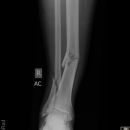

distaler Unterschenkelschaft

Spiralfraktur Tibia